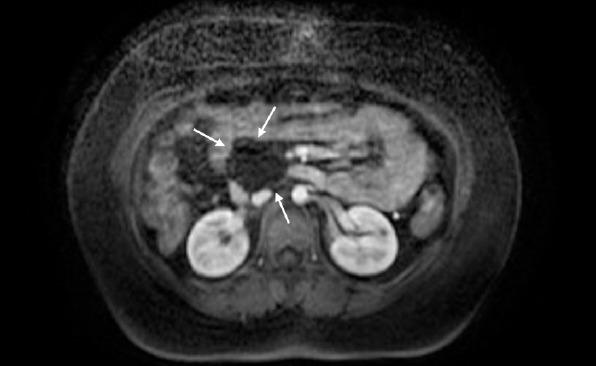

Agenesis of the dorsal pancreas (ADP) is extremely rare disease with no specific symptoms and there is no clear pathogenesis. Approximately half of the affected individuals develop diabetes resulting from reduced islet cell mass secondary to lack of endocrine structures. In this case, we aimed to present a 17-year-old female patient with ADP accompanied by a pancreatic cyst.

背侧胰腺发育不全(ADP)是一种极为罕见的疾病,没有特定症状,发病机制也不明确。大约一半的患者会因内分泌结构缺失导致胰岛细胞数量减少而患上糖尿病。在此病例中,我们旨在介绍一名17岁患有ADP并伴有胰腺囊肿的女性患者。